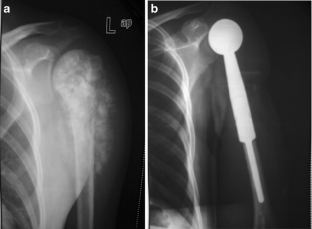

Fig. 1